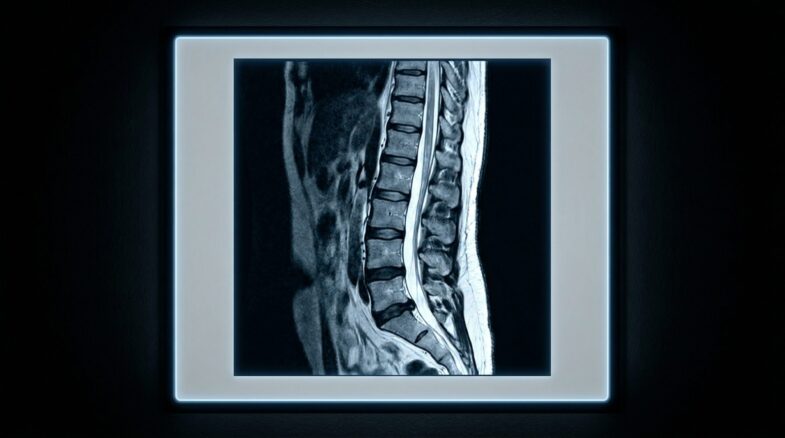

Advanced Spine Surgery

Microscopic and endoscopic spinal surgeries including disc excision, artificial disc implantation, vertebral fracture fixation, and treatment of cervical and lumbar disc herniation.